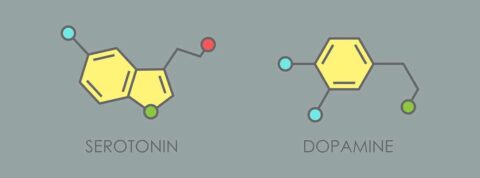

La dopamina y la serotonina son dos neurotransmisores, es decir, moléculas que se encargan de llevar un mensaje desde las neuronas que lo producen hacia otras células.